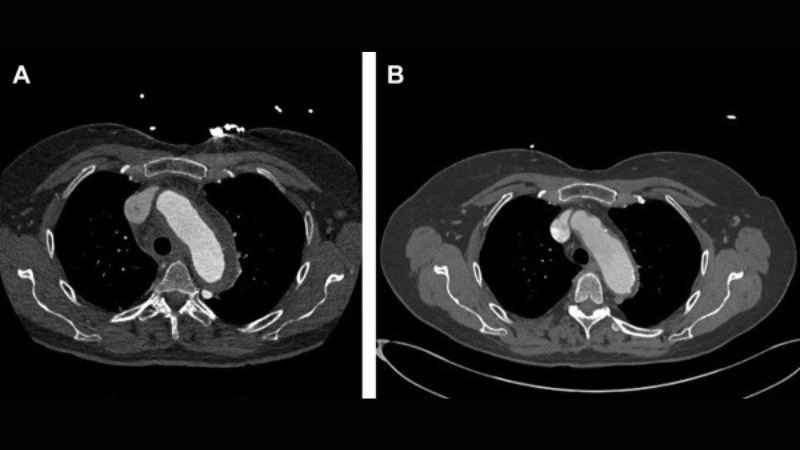

Aortitis diagnosis with advanced medical imaging